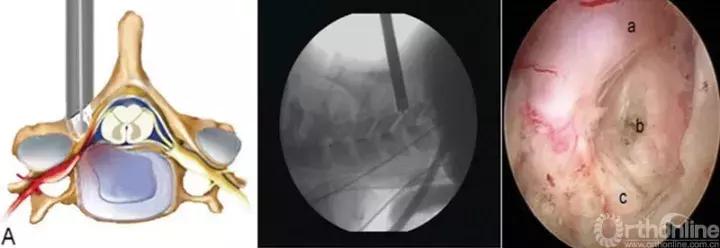

颈椎后路经椎间孔入路骨性标志点为“V”点,操作时注意“靶区触骨,动力先行,显根上下,脊髓勿碰。”也就是说,建立靶区应落到V点骨性结构部分,再用动力沿V点磨除外层皮质骨,黄韧带边缘会自然显露,再用Kerrison钳扩大显露神经根肩部与腋部,用神经勾进行探查和髓核摘除,手术全程都要注意保护脊髓,避免通过后方进行椎间隙髓核摘除这一危险操作。

颈椎前路:

与颈椎后路相比,前路由于入路复杂、毗邻结构重要和颈椎解剖限制,通过前路进行髓核摘除有较大争议。对于平间隙水平的突出,可以通过经椎间隙或椎间孔进行减压操作,对于移位到椎体后缘者,可以考虑经椎体进行,但操作难度较大。颈椎前路经皮内镜手术高的围手术期并发症,以及远期疗效问题,仍然需要我们对这一入路,通过循证医学角度,来科学看待,客观分析。